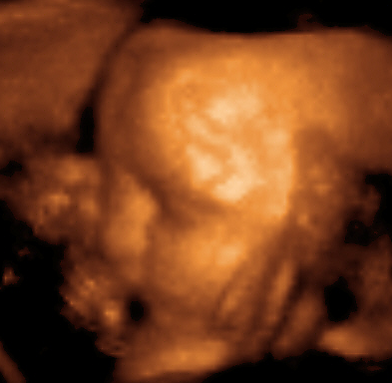

Ультразвуковое исследование используется для изучения внутренних половых органов женщины, состояния беременной матки, анатомии и мониторинга внутриутробного развития плода.

Этот эффект широко применяется в акушерстве, так как звуки, идущие от матки, легко регистрируются. На ранней стадии беременности звук проходит через мочевой пузырь. Когда матка наполняется жидкостью, она сама начинает проводить звук. Положение плаценты определяется по звукам протекающей через неё крови, а через 9 — 10 недель с момента образования плода прослушивается биение его сердца. С помощью ультразвукового исследования можно также определять количество зародышей или констатировать смерть плода.

Диагностическое ультразвуковое исследование плода также в целом рассматривается как безопасный метод для применения в течение беременности. Эта диагностическая процедура должна применяться, только если есть веские медицинские показания, с таким наименьшим возможным сроком воздействия ультразвука, который позволит получить необходимую диагностическую информацию, то есть по принципу минимального допустимого или АЛАРА-принципу.